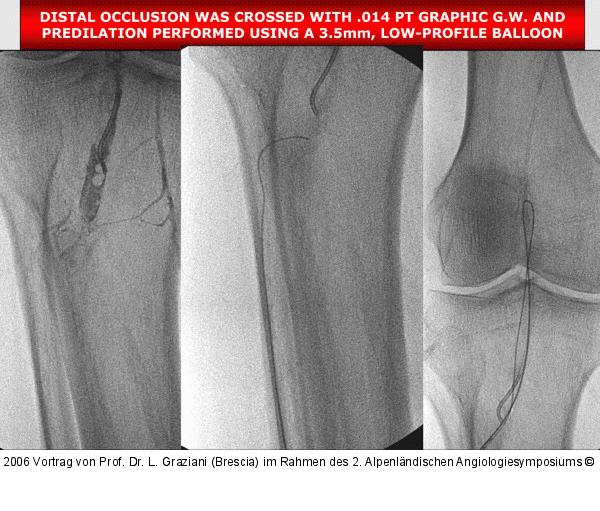

PTA of the foot arteries in diabetics: Extremities Extreme Angioplasty

Abbildung 66: P.O.B.A.